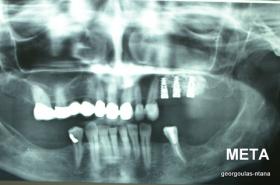

ΑΝΟΙΚΤΗ ΑΝΥΨΩΣΗ ΙΓΜΟΡΕΙΟΥ Κ ΤΟΠΟΘΕΤΗΣΗ 3 ΕΜΦΥΤΕΥΜΑΤΩΝ

Στην ασθενή αυτή πραγματοποιήθηκε ανοικτή ανύψωση ιγμορείου άνω αριστερά. Σε πρώτη φάση πραγματοποιήθηκε η οστική αύξηση και 6 μήνες μετά τοποθετήθηκαν 3 εμφυτεύματα. Τόσο στην πανοραμική όσο και στην τομογραφία κωνικής δέσμης (CBCT) που πραγματοποιήθηκαν 6 μήνες μετά την ανύψωση είναι εμφανής ο σχηματισμός οστού. Η τελευταία ακτινογραφία και φωτογραφία λήφθηκαν 5 χρόνια μετά την προσθετική αποκατάσταση.